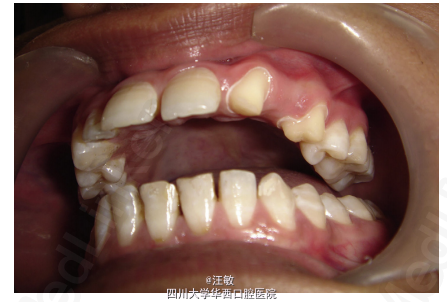

计划拔除左上滞留乳尖牙,拔除后可考虑活动或固定修复。由于经济等问题患者选择固定桥修复,以23、24为基牙修复缺牙间隙。

牙异位在临床中比较常见。病例中的滞留乳牙拔除后,如果经济、牙槽骨等条件许可,最佳选择为种植修复。如果患者认为种植修复期间缺牙影像美观,可以制作活动义齿解决缺牙美观问题。 do:org/10.1016/j.jobcr.2014.07.001